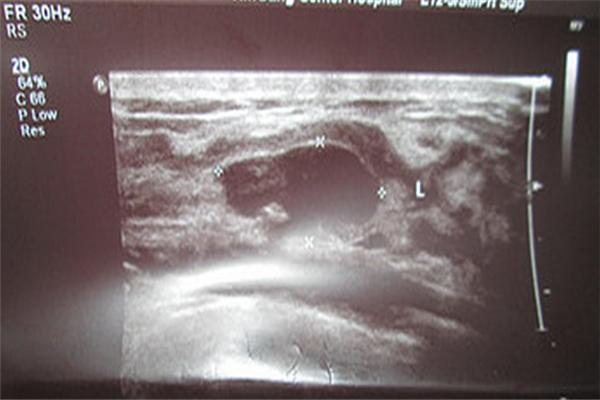

【12岁女孩潇潇两侧胸部一个大一个小,且大小过于悬殊,起初以为是发育不均,直至上周,潇潇的妈妈发现女儿的右胸实在太大,明显比左胸大了好几圈,才觉得不正常,赶紧带着女儿到医院检查,经B超检查,医生发现潇潇右侧乳房有个直径10厘米的肿块,质地较硬,初步判断是巨大乳腺纤维瘤,由于肿块太大,只能进行开放手术,成功将肿块切除。】

乳腺纤维瘤是由腺上皮和纤维组织两种成分混合组成的一种良性肿瘤,好发于青年女性,主要与患者体内性激素水平失衡有关,主要为乳房无痛性肿块,很少伴有乳房疼痛或乳头溢液,单发肿块居多,亦可多发,也可两侧乳房同时或先后触及肿块,多为圆形或椭圆形,极易认为是发育不均导致两侧胸部大小不均。而12岁的潇潇正处于青春发育期,过多摄入油炸、含有雌激素的食物有关。而精神压力大、长期熬夜、爱生闷气也都是该病的诱发因素。